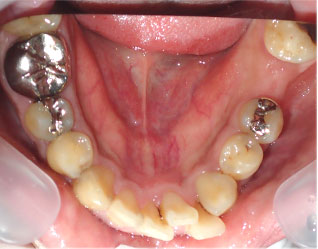

- ブリッジ 症例写真 B-0093スタンダードジルコニア9本、スタンダードジルコニア7本 男性モニターの方です。

Before

After詳細はコチラ

セラミック法によるブリッジ治療の症例

施術 スタンダードジルコニア9本、スタンダードジルコニア7本 - コメント

この方は前歯の歯並びと奥歯の虫歯、欠損の治療を希望されました。

前歯の歯並びはセラミック法で治療しました。

奥歯の欠損はブリッジで治療しました。

また、下の前歯も歯周病で1本抜歯になりましたのでその部分もブリッジ治療しています。

当院ではこの様にいろいろな歯のお悩みがあっても同時進行で治療する事が可能です。